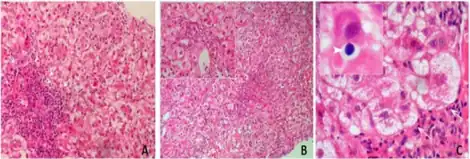

Rarely, cholestatic jaundice (also referred to as cholestatic hepatitis, a form of liver toxicity) has been associated with amoxicillin/clavulanic acid. The reaction may occur up to several weeks after treatment has stopped, and usually takes weeks to resolve. It is more frequent in men, older people, and those who have taken long courses of treatment; the estimated overall incidence is one in 100,000 exposures.[12] In the United Kingdom, co-amoxiclav carries a warning from the Committee on Safety of Medicines to this effect.[11]